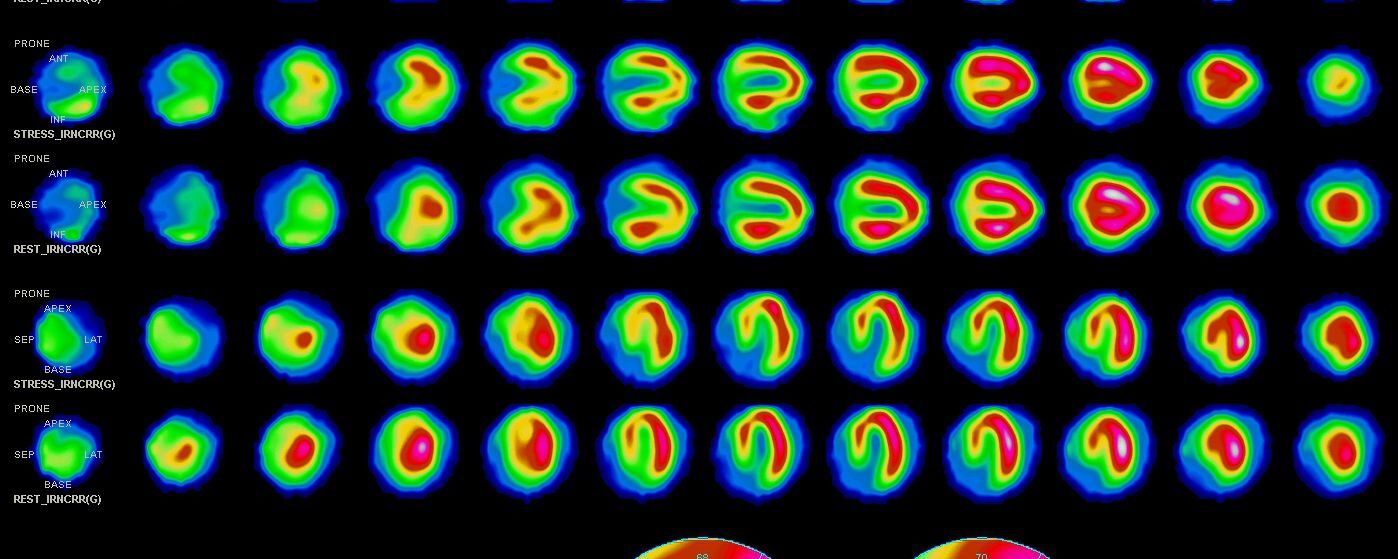

Dépistage d’ischémie myocardique chez un patient de 57 ans.

ECG de repos : BBG et tachycardie sinusale à 110 bpm

Epreuve d’effort pharmacologique seule: Bonne tolérance au Dipyridamole sans anomalie clinique ou modification ECG